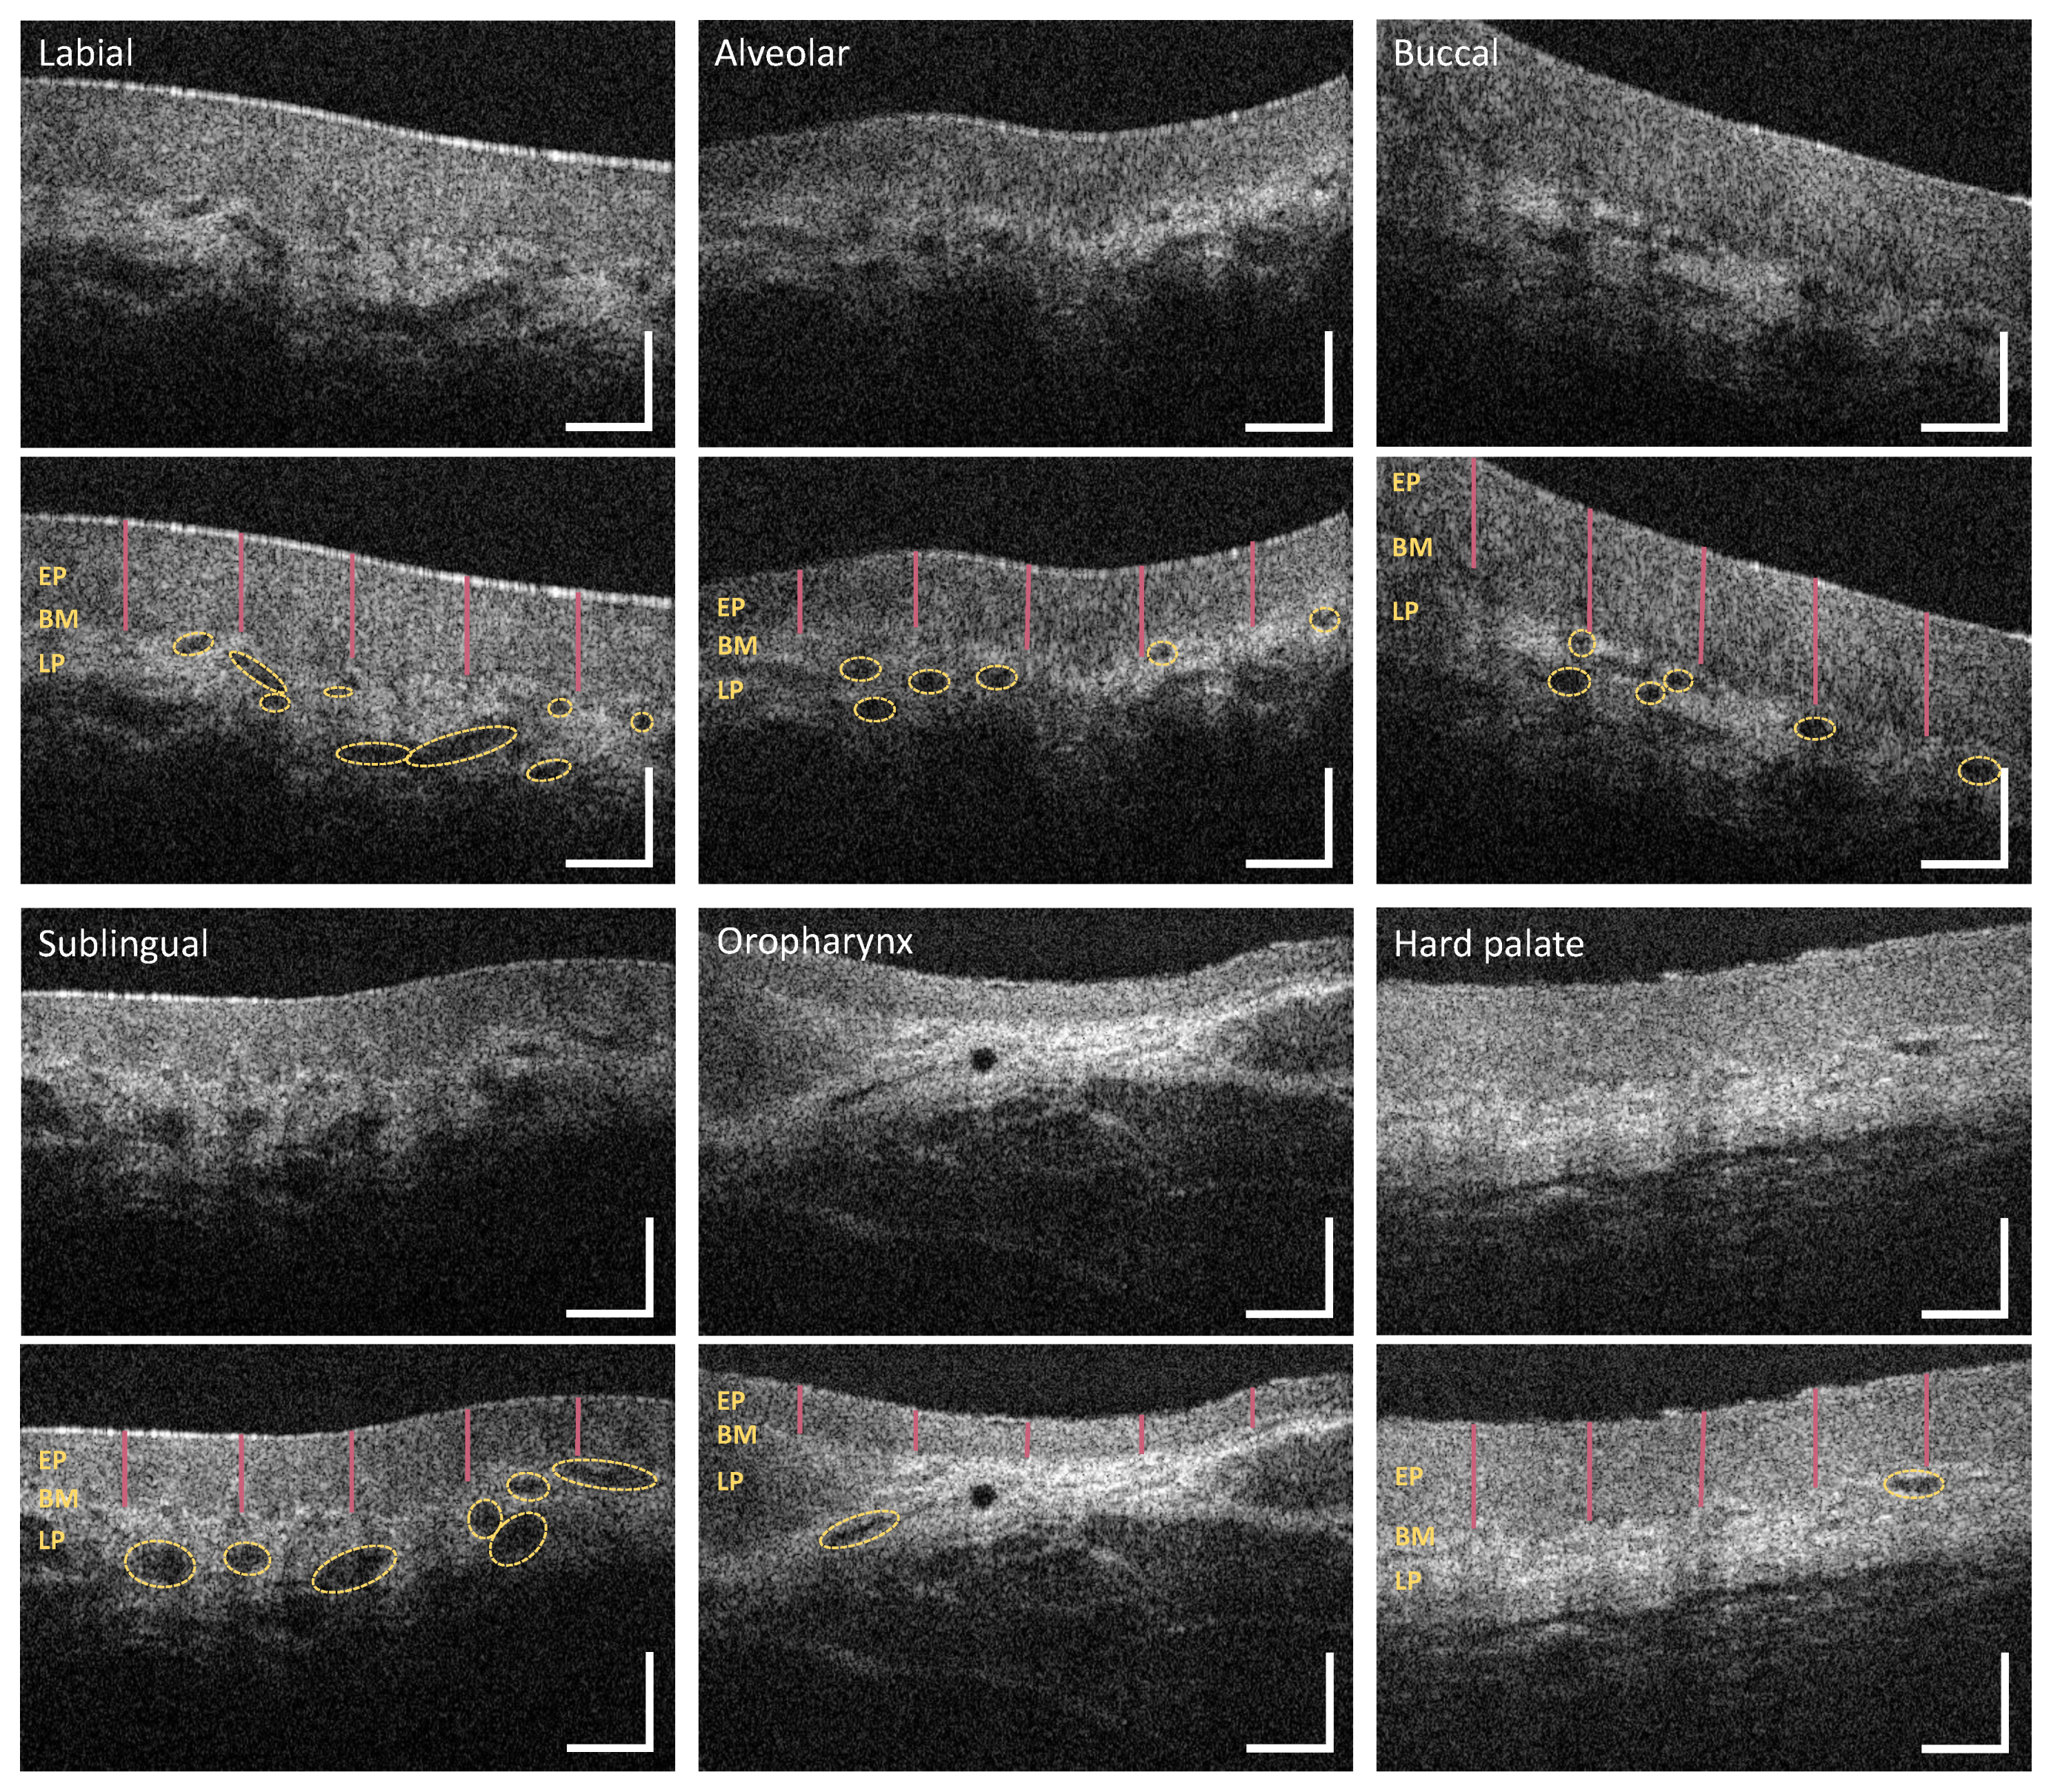

3.1. Labial and Alveolar Mucosa

3.2. Buccal Mucosa

3.3. Sublingual Mucosa

3.4. Hard Palate

3.5. Soft Palate and Oropharynx